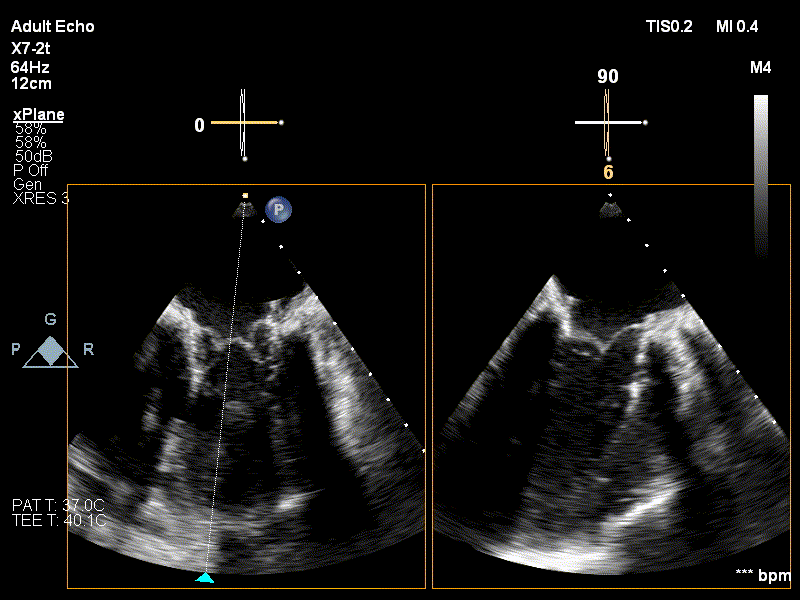

4. Ecografie 3D post implant proteză biologică Edwards Sapien 3 în poziție mitrală (TAVI in MAC)

Procedura a fost efectuată cu succes, proteza fiind poziționată corect la nivelul valvei mitrale native, fără leak-uri paraprotetice și cu un gradient mitral maxim/mediu de 7/3 mmHg. De asemenea, nu s-au înregistrat semne de obstrucție în tractul de ieșire al ventriculului stâng. În plus, reevaluările ecocardiografice post-procedurale au confirmat că proteza funcționează normal.

5. Ecografie transesofagiană intraprocedurală la finalul procedurii, proteza corect poziționată la nivelul valvei mitrale, cuspe cu mobilitate bună